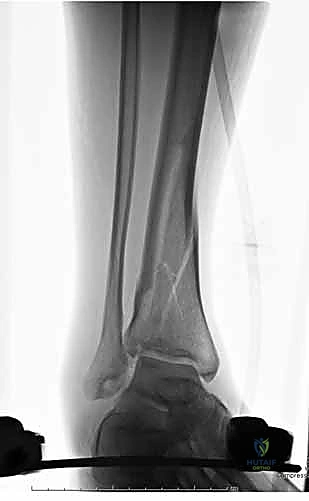

1. التقييم والتحضير (Pre-operative)

بمجرد وصول المريض إلى الطوارئ، يتم إنعاشه وإعطاؤه المضادات الحيوية الوريدية فوراً (خاصة في الكسور المفتوحة). يتم أخذ صور أشعة سينية وأحياناً أشعة مقطعية (CT Scan) لفهم نمط الكسر بدقة.

4. رد الكسر (Fracture Reduction)

يقوم الجراح بسحب الساق وتحريك العظام لإعادتها إلى محاذاتها التشريحية الصحيحة (الطول، الدوران، والزوايا).